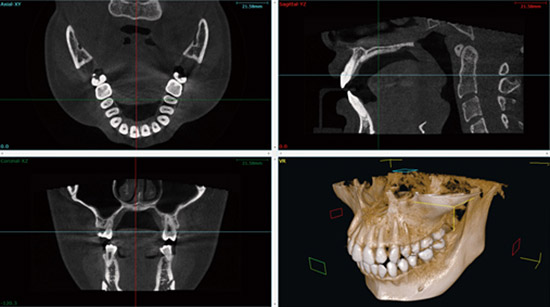

当院ではアールエフ社のNAOMI CT・セファロレントゲンを使用しています。着席での使用のため、足腰が不自由な方でも楽な状態で撮影が可能です。

根管や歯周病の治療、嚢胞、智歯抜歯、インプラントの治療計画、そして2次元の撮影で不明な部分も3次元で画像診断が可能です。

頭部全体のX線写真を撮影できるシステムです。特に歯や顎の骨、頭蓋骨の関係性を分析する性能に優れており、患者さんの歯の位置や噛み合わせの状態、顎の位置などの骨格的な問題を正確に把握するために使用されます。

これにより精密さが求められる矯正治療の計画、どのような治療が必要かの判断ができます。顔の輪郭や骨格がどのように変化するかの分析ができますので、成長期のお子さんや顔のバランスが気になる成人患者さんの診察にも利用します。